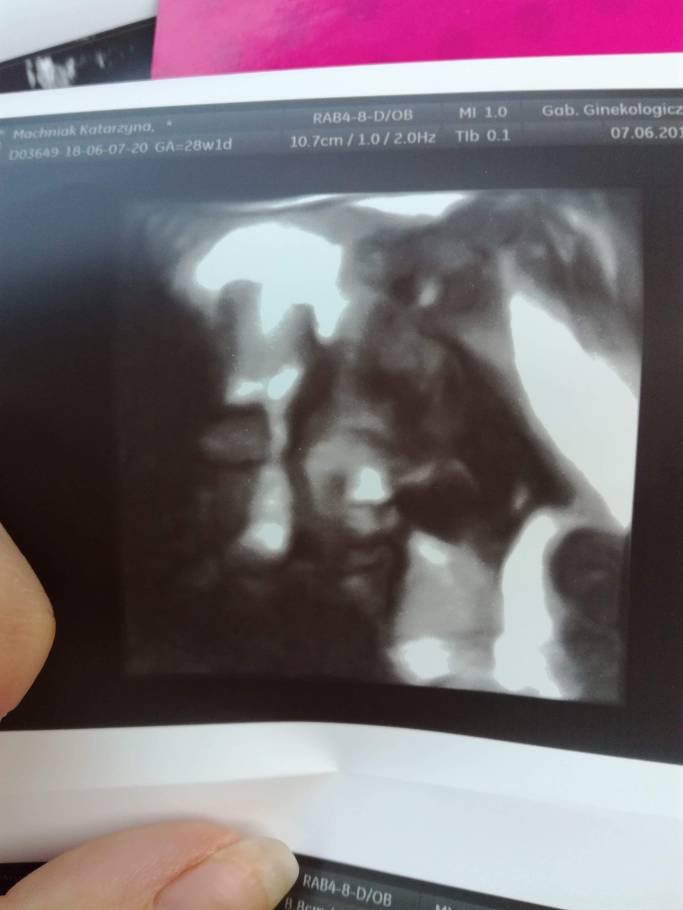

A tak Maja u nas wyglądala w 29tc na ostatnich prenatalnych

Na pierwszym zdjęciu córka a na drugim syniuZobacz załącznik 881597Zobacz załącznik 881598